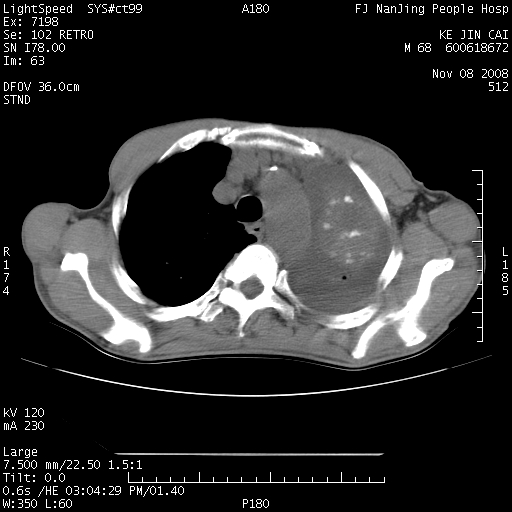

是个很有看头的病例,咋人气那么不旺?没多少人兴趣呢?这个病例几大怪:1   恶性肿瘤侵犯心肌左房怪,心肌一般不会被恶性肿瘤侵犯吧?2   左下肺均匀实变怪,内无含气,有别一般不张实变,含气肺泡完全为液体取代,而非一般不张实变的肺萎陷,冷不丁还以为是肿大的脾脏3   肿瘤本身怪,像tb肺不张4   这么有看头的病例没人气怪。呵呵。

左肺恶性肿瘤侵犯肺动脉,左心房内瘤栓,胸膜转移。